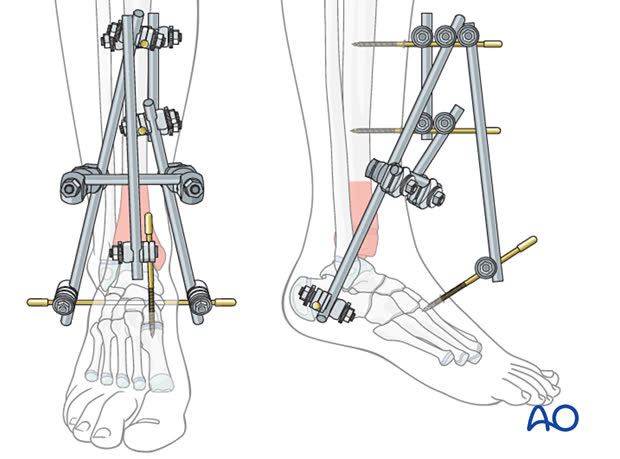

Этапное лечение (протокол Sirkin) остаётся золотым стандартом при переломах пилона с повреждением мягких тканей.

Этап 1 (день 0–1):

- Временная чрескостная фиксация аппаратом внешней фиксации (АВФ) — дельта-рама или блокирующая конструкция через голеностопный сустав (возможно также использование классических конструкций)

- Репозиция малоберцовой кости и остеосинтез

- Обработка раны при открытом переломе

- Опционально: ограниченная репозиция и фиксация большеберцовой кости (LTRF — Limited Tibial Reduction and Fixation) при первичной операции

Циркулярная внешняя фиксация

Мета-анализ (Malik-Tabassum et al., Injury, 2020, N=239): сопоставимая частота несращения, неправильного сращения и инфекции между ORIF и циркулярной внешней фиксацией. При ORIF выше частота удаления металлоконструкций (RR 5,68, P=0,04), но ниже частота посттравматического артроза (RR 0,48, P=0,003).

Показания: открытые переломы с тяжёлым повреждением мягких тканей, когда внутренняя фиксация противопоказана; пациенты с сопутствующей сосудистой патологией нижних конечностей.

| Циркулярная ВФ (Илизарова) | 43C3 с тяжёлым повреждением мягких тканей | Не требует диссекции, ранняя нагрузка | Инфекция спиц 5–20%, контрактуры |

| Гибридная ВФ | Тяжёлые мягкие ткани + необходимость суставной репозиции | Ограниченная артротомия + защита мягких тканей | Сложность конструкции |